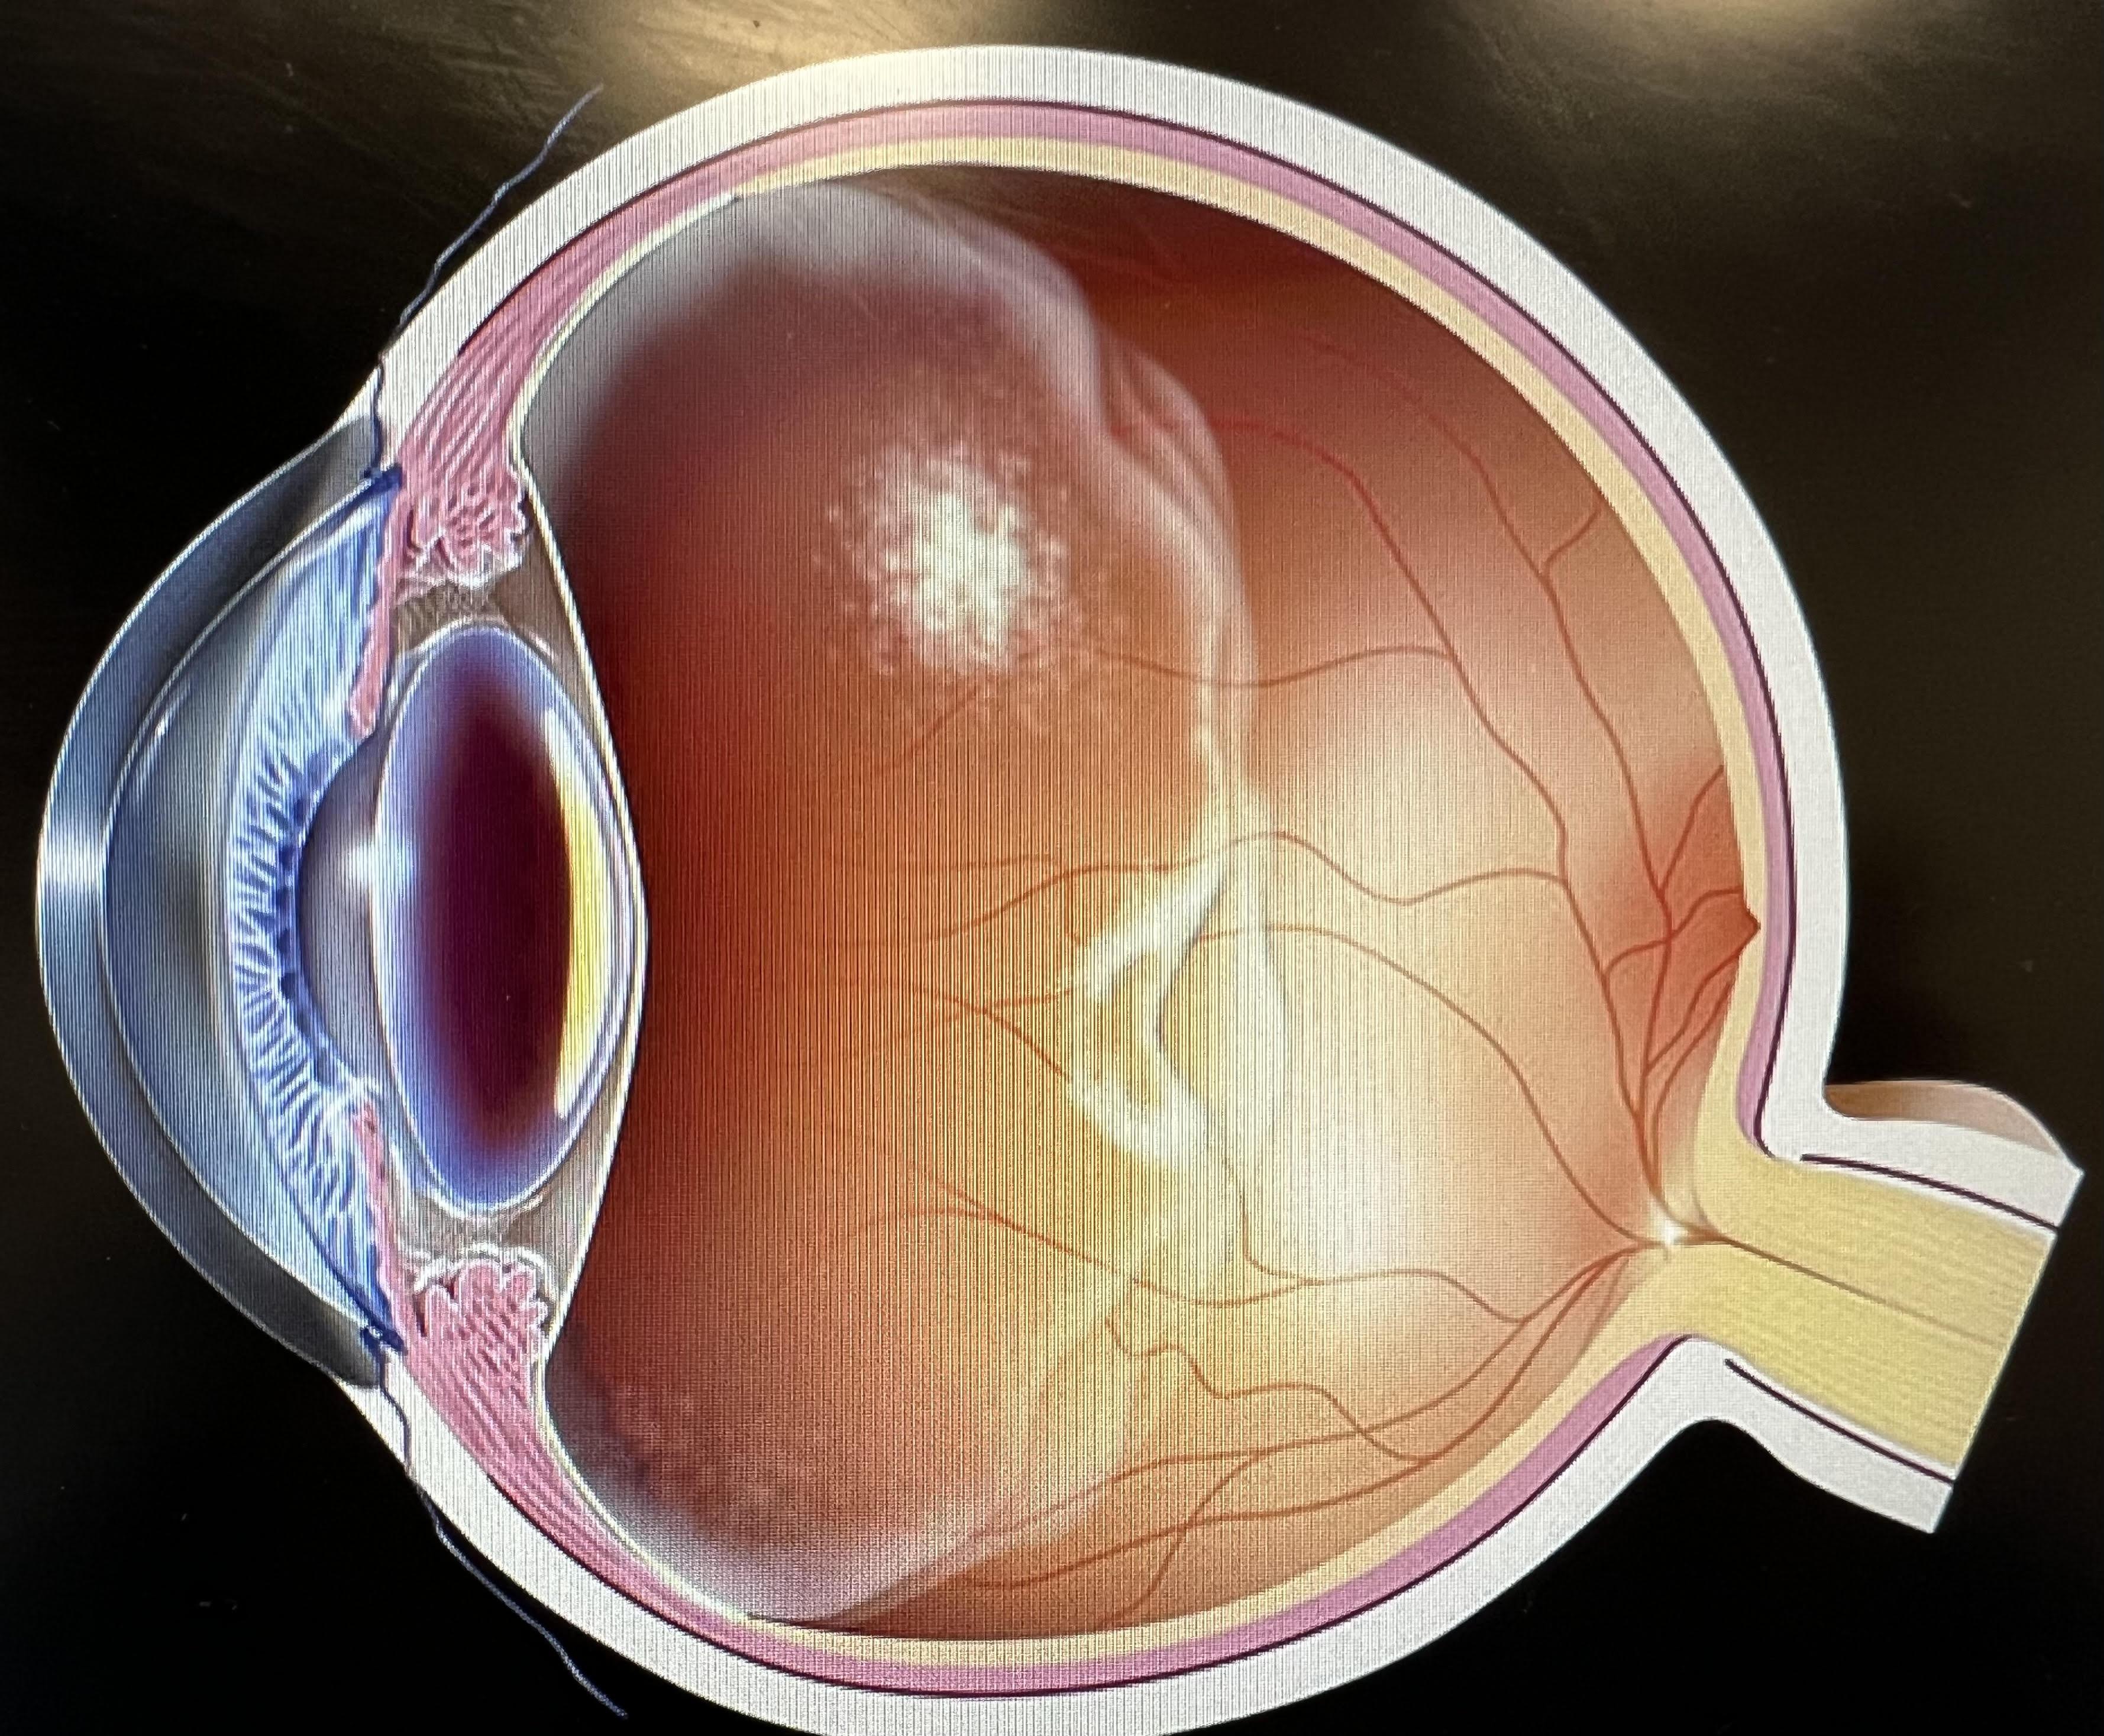

玻璃體後脫離。

玻璃體是眼球內一個啫喱狀的組織,玻璃體會隨年齡增長而退化,慢慢液化、收縮,最後與視網膜完全分離,這就是玻璃體後脫離。收縮過程中有機會拉扯到視網膜,導致視網膜破洞甚至脫落,延誤治療可對視力造成永久性損害,嚴重可致盲。

我們視物就像目光透過一個金魚缸,如果水變得混濁,就會看到有半透明東西在眼前飄浮,這就是飛蚊症了。當玻璃體老化時會變得混濁,便會出現飛蚊症狀,若因玻璃體老化萎縮而撕扯到視網膜,視線就會出現閃光,像有人在用閃光燈拍照一般。如果視網膜因此而破洞,飛蚊症狀會急劇增加,也會出現閃光視覺,一旦有這些狀況發生,就要盡快求醫做眼科檢查,若然置之不理視網膜可能會完全脫落,導致視力驟降,或周邊視野有黑影,彷似戲院落幕一樣,嚴重甚至眼前有大片黑影,造成不可逆轉的視力缺失或失明。